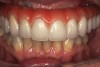

The final restorative solution can be either fixed or removable. Fixed solutions may include: computer-aided designed/computer-aided manufactured (CAD/CAM) fixed prostheses with a titanium (Figure 8 and Figure 9) or zirconia (Figure 10 and Figure 11) framework; fixed prostheses with a CAD/CAM-designed titanium or zirconia framework with acrylic veneering (Figure 12); or fixed prostheses with cast metal and veneering porcelain. Removable solutions may include a milled bar overdenture with attachments, such as locators or an MK1 Attachment (MK1 Dental Attachment GMBH, www.MK1.de) (Figure 13). Removable solutions that allow for simpler hygiene-related practices may be beneficial for elderly patients. In addition, removable solutions may be necessary for patients who require sufficient lip support, as the flange on a removable solution can assist in supporting the contours of the face. It is important to discuss the relative advantages and disadvantages of fixed and removable solutions during the informed consent process.

The long-term efficacy of the All-on-4 technique and its numerous advantages, such as immediate function and esthetics, reduced morbidity, high patient satisfaction, and relatively lower costs, should be considered when assessing treatment options for an edentulous jaw.

Fig 9. Intraoral view of the titanium bridge framework with individual lithium-disilicate crowns.

Figure 9

Fig 10. The full-arch zirconia framework with individual lithium-disilicate crowns, which were individually luted in the laboratory.

Figure 10